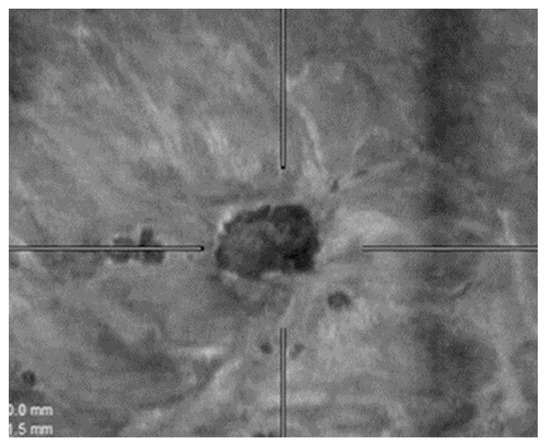

2.4. ABVS Interpretation

- Zheng, F.Y.; Yan, L.X.; Huang, B.J.; Xia, H.-S.; Wang, X.; Lu, Q.; Li, C.-X.; Wang, W.-P. Comparison of retraction phenomenon and BI-RADS-US descriptors in differentiating benign and malignant breast masses using an automated breast volume scanner. Eur. J. Radiol. 2015, 84, 2123–2129. [Google Scholar] [CrossRef] [PubMed]